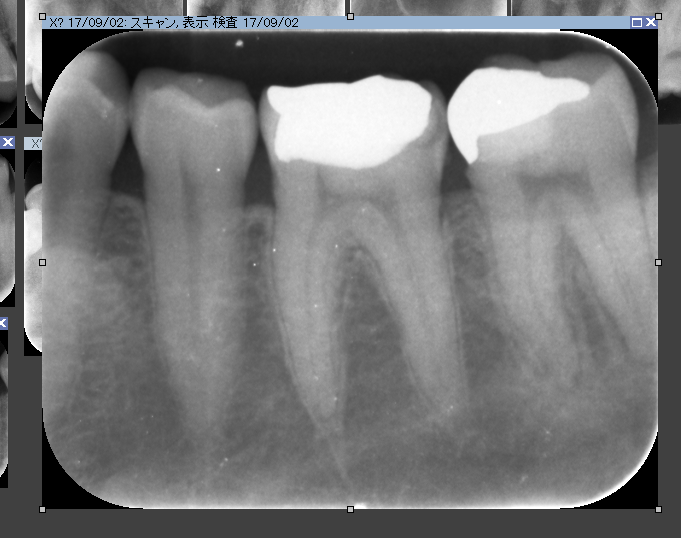

いつも通りまず歯科ドックをして原因を調べます。ドックの結果神経が死んでいました。しかし今回わからなかったのは分岐部といって歯の又の部分にも病変がありました。。。

CTとデンタルをみると髄床から何か管か破折線か見えます。なんだろう。これが分岐部病変の原因ではないかと思います。歯科ドックをしたからここまでわかりました。

ん?近心根の中に2根(珍しい)1つは分岐部へ。

非常に珍しいケース。近心の根管の中に分岐部があり根管がご覧の様に縦に並んでいました。根管の形態はご覧の様に様々。だから時間と精密さが求められます。